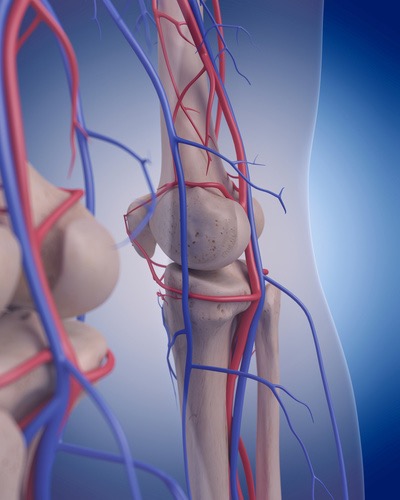

脛骨神経は、坐骨神経に由来する総腓骨神経と並ぶやや径の大きな神経で、解剖学的正位で、下腿部においては、膝窩の情報で脛骨に沿って内側を走行します。下肢は坐骨神経の影響が多いと考えられていますが、実はこの脛骨神経由来の症状は臨床上とても多く経験します。特に膝窩部に部分でこの脛骨神経が絞扼されると腰痛を引き起こすことがとても多いです。

この脛骨神経のリリーステクニックを学ぶことであなたは、、、

この弓状膝窩靭帯を治療したことはありますか?この靭帯は腓骨頭の外側面から膝窩筋腱を横切って、関節包に付着しています。このように関節包に付着するということは当然関節包に刺激を加え、痛みを生じさせます。そして関節包自体もしくは隣接する膝窩筋に対しても滑走性の低下、筋高度を高めてしまいます。膝痛の最終調整には欠かせない靭帯調整リリーステクニックとなります。

この弓状膝窩靭帯リリーステクニックを学ぶことであなたは、、、